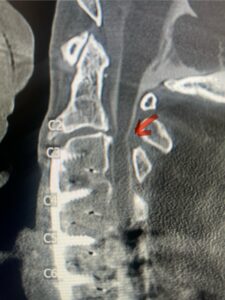

Fig 1: Sagittal cervical CT myelogram demonstrating spinal cord compression at C2-3 above the prior anterior cervical fusion (red arrow)

This 62 year-old female who had a prior ACDF from C3-C7 by an outside surgeon in 2009 and subsequent C5-C7 posterior cervical decompression and fusion in 2015 by our team, presents with progressive numbness, pain, and weakness of her arms. Above her prior anterior fusion, she had next segment degeneration with spinal stenosis resulting in spinal cord compression at C2-3 (Fig. 1).

Patient had an existing peripheral occipital nerve stimulator and therefore we had ordered a myelogram since it was not MRI compatible. The patient underwent a decompressive laminectomy and in situ fusion at C2-3. Care was made to preserve a good portion of the C2-3 facets bilaterally. It was felt that her C2 pars anatomically were not favorable to accept pars screws given the proximity of the vertebral foramen with a resultant narrow par (Fig. 2). She also had a normal C2-3 vertebral alignment. Post-operatively she had improvement of her arm pain and strength in right arm. In this case we made a decision to decompress the patient posteriorly given her prior anterior surgery, a more difficult approach to C23 disc space, and significant C23 disc collapse. A posterior approach was favorable in our opinion given the prior posterior surgery was more inferior with less scarring likely to be encountered in the C1-3 region. A posterior decompression also can yield a more adequate spinal cord decompression. Since we elected not to place pars screws because of her anatomy, and perform an in-situ fusion, careful attention was made to preserve as much of the C23 facet complex as possible.